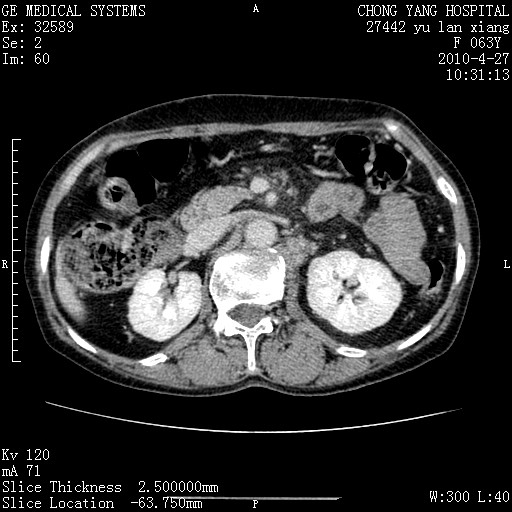

标题: CT26066:F63Y 上腹正中压痛半月,CA199:7400u/ml,MR示胰腺炎伴 [打印本页]

胰腺癌侵犯腹腔动脉干-分支、胃壁、左侧膈肌伴胰周及腹膜后淋巴结转移、胆囊切除术后。

胰腺癌侵犯腹腔动脉干-分支、胃壁、左侧膈肌伴胰周及腹膜后淋巴结转移、胆囊未显影。